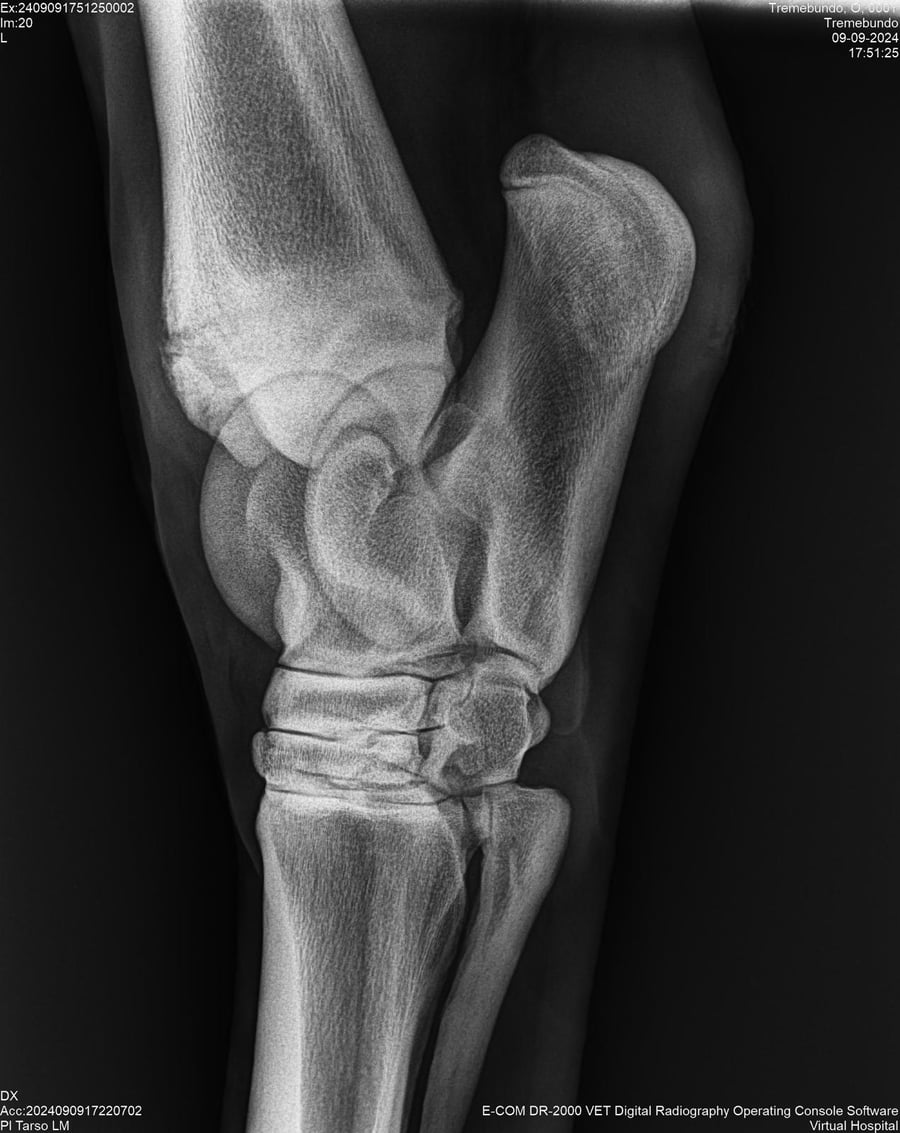

LOTE 37, TREMEBUNDO

Identificador: #291140-

Generacion 2022